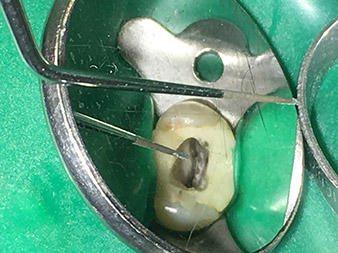

The 3E tip was specially designed for the removal of broken-off and fractured root canal instruments. In my experience, this is possible from the coronal section down to the central canal section with corresponding magnification (min. 3.6x dental loupes, ideally microscope).

This step should be performed with a non-diamond-coated, sharply tapered tip, with which it is possible to expose the fractured fragments of the instrument in the dentine region under microscopic control. In addition, the instrument is perfectly suited to exposing broken-off root canal posts coronally so that they can subsequently be shaken out with the 5E tip.

I also use this tip a lot to clear dentine overhangs away from thin canals and make the canal openings clearly visible. It is particularly well suited to applications in the second mesiobuccal canal on the maxillary molars or in cases of obturated canals. In the case of thin canals, the function is almost identical to that of the 6E tip, which works optimally in medium-sized to wide canals.

Dr. Nouraie: The use of ultrasonic tips allows targeted, atraumatic, minimal removal of substance at the desired site (e.g., when exposing the canal openings, rounding off the cavity floor and exposing broken-off instruments or posts as well as when processing coronal canal sections).

Canal transitions can be smoothed and rounded off with more precision than when using burs. The activation of the rinsing fluid in particular offers enormous advantages that cannot be guaranteed with other instruments. The special instruments from W&H make it possible to perform completely new indications minimally invasively such as revision of broken-off tips and posts.

Visual aids such as dental loupes or even better a surgical microscope should be employed for all indications in the canal. In addition, I also think it is important that all the applications in the canal – with the exception of the activation of the rinsing fluid – are performed by specialized colleagues with corresponding experience and the necessary expertise in the field.